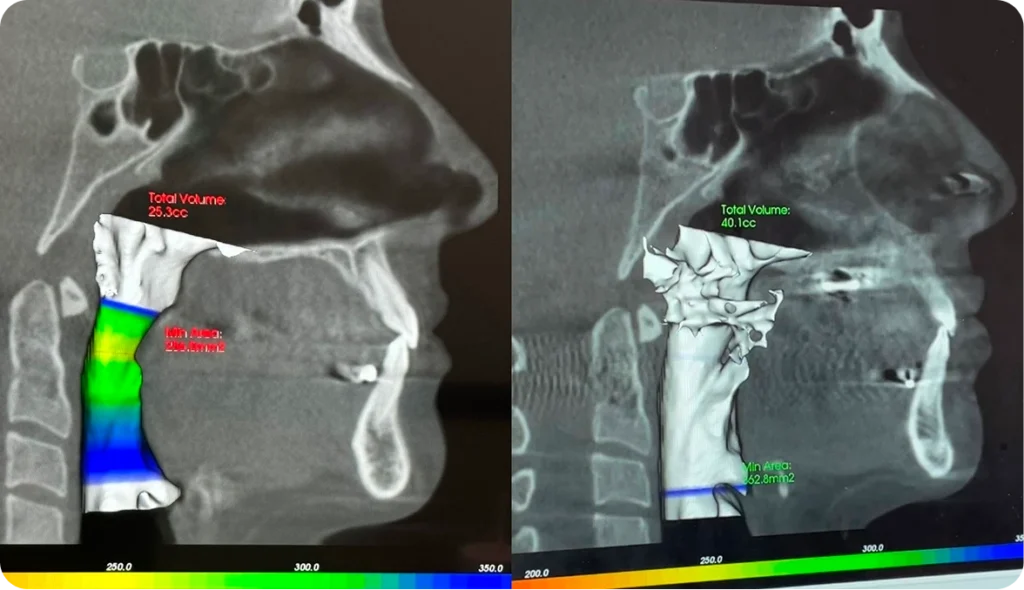

MARPE is a maxillary expander that is supported by tiny mini screws placed in the upper palate. Unlike traditional expanders that push on the teeth, MARPE’s unique placement in the roof of the mouth creates skeletal changes. This not only increases upper arch width, but also gives more nasal breathing volume and development in the midface. This is why MARPE is often the best non-surgical alternative for adults who previously had no other options.

We begin with a full airway, skeletal, and bite assessment using CBCT imaging, digital scans, and functional evaluation.